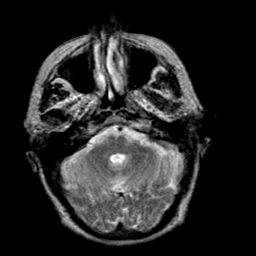

Creutzfeld-Jakob disease: T2-weighted MR -- Slice #5

[Home][Help][Clinical] Slice 5